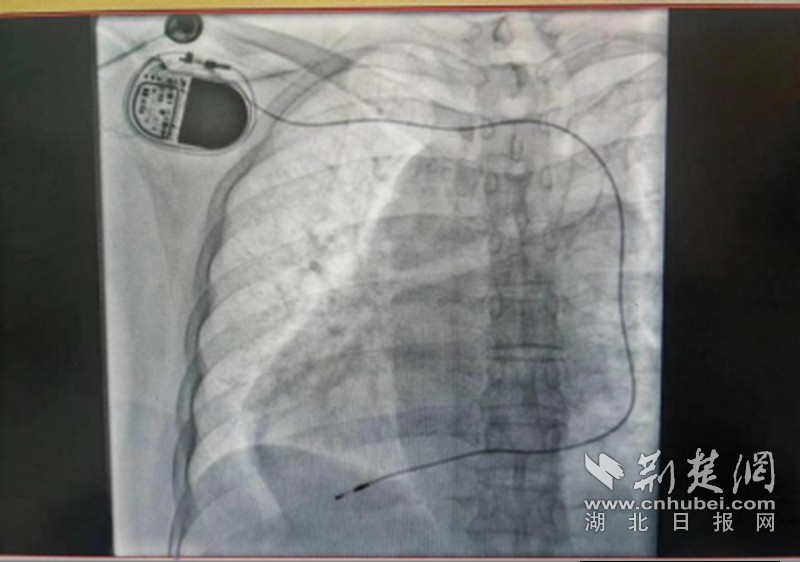

考慮以上種種因素,該院心血管內(nèi)科介入團(tuán)隊(duì)經(jīng)過(guò)認(rèn)真且詳細(xì)的術(shù)前討論,在做好各種預(yù)案,與患者及家屬充分溝通后,決定實(shí)施心臟永久起搏器安置術(shù)。6月19日下午,由醫(yī)院心血管內(nèi)科主任蘭江、副主任辜強(qiáng)、主治醫(yī)師張華、陳文婷、陳明慧等組成的介入團(tuán)隊(duì),為申阿姨實(shí)施了永久起搏器植入術(shù)。手術(shù)歷時(shí)近3小時(shí),蘭江主任團(tuán)隊(duì)克服了患者鎖骨下靜脈變異、需要在造影下重新穿刺等重重難關(guān),最終成功為患者在右側(cè)胸壁植入了永久單腔起搏器,植入后各項(xiàng)參數(shù)良好,術(shù)后患者頭暈癥狀有所改善,無(wú)任何并發(fā)癥,近日已順利康復(fù)出院,患者及家屬對(duì)治療效果非常滿意。

一般而言,普通人的心臟偏左,位于左胸腔,但也有一部分人長(zhǎng)在了右側(cè),其心房、心室和大血管的位置宛如正常心臟的鏡中象,被稱為“右位心”,又稱“鏡面心”,是一種少見(jiàn)的先天性心血管病,在人群中約占1%。而為右位心患者植入永久起搏器,目前國(guó)內(nèi)外僅有個(gè)案報(bào)道。